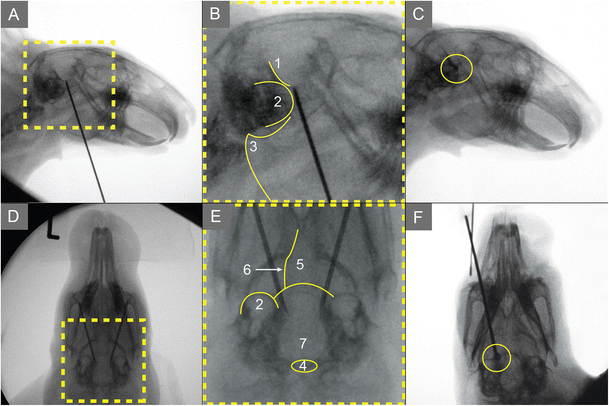

穿刺技术和方法:定位和方向:兔子俯卧。头部被剃光,标记为图所示。在侧视图中,FO项目约在颧弓下缘和髁状突的后缘的交点(髁突)。套管的入口点横向投影在下颌角的突出处。

穿刺过程:套管的入口正好位于下颌的内缘。套管在FO方向上与pi线呈45度角前进。

尸体经皮穿刺过程模拟:在家兔身上,经皮引导经颊部插管到达FO类似人类,是不可能的。为此,我们切换到下颌的方法和对16具尸体进行了30次经皮手术。通过X线片和随后的脑解剖保证最佳针的位置。由于我们的目的是为实验性经皮手术提供一个手册,在结果部分中描述了方法和使用的设备。